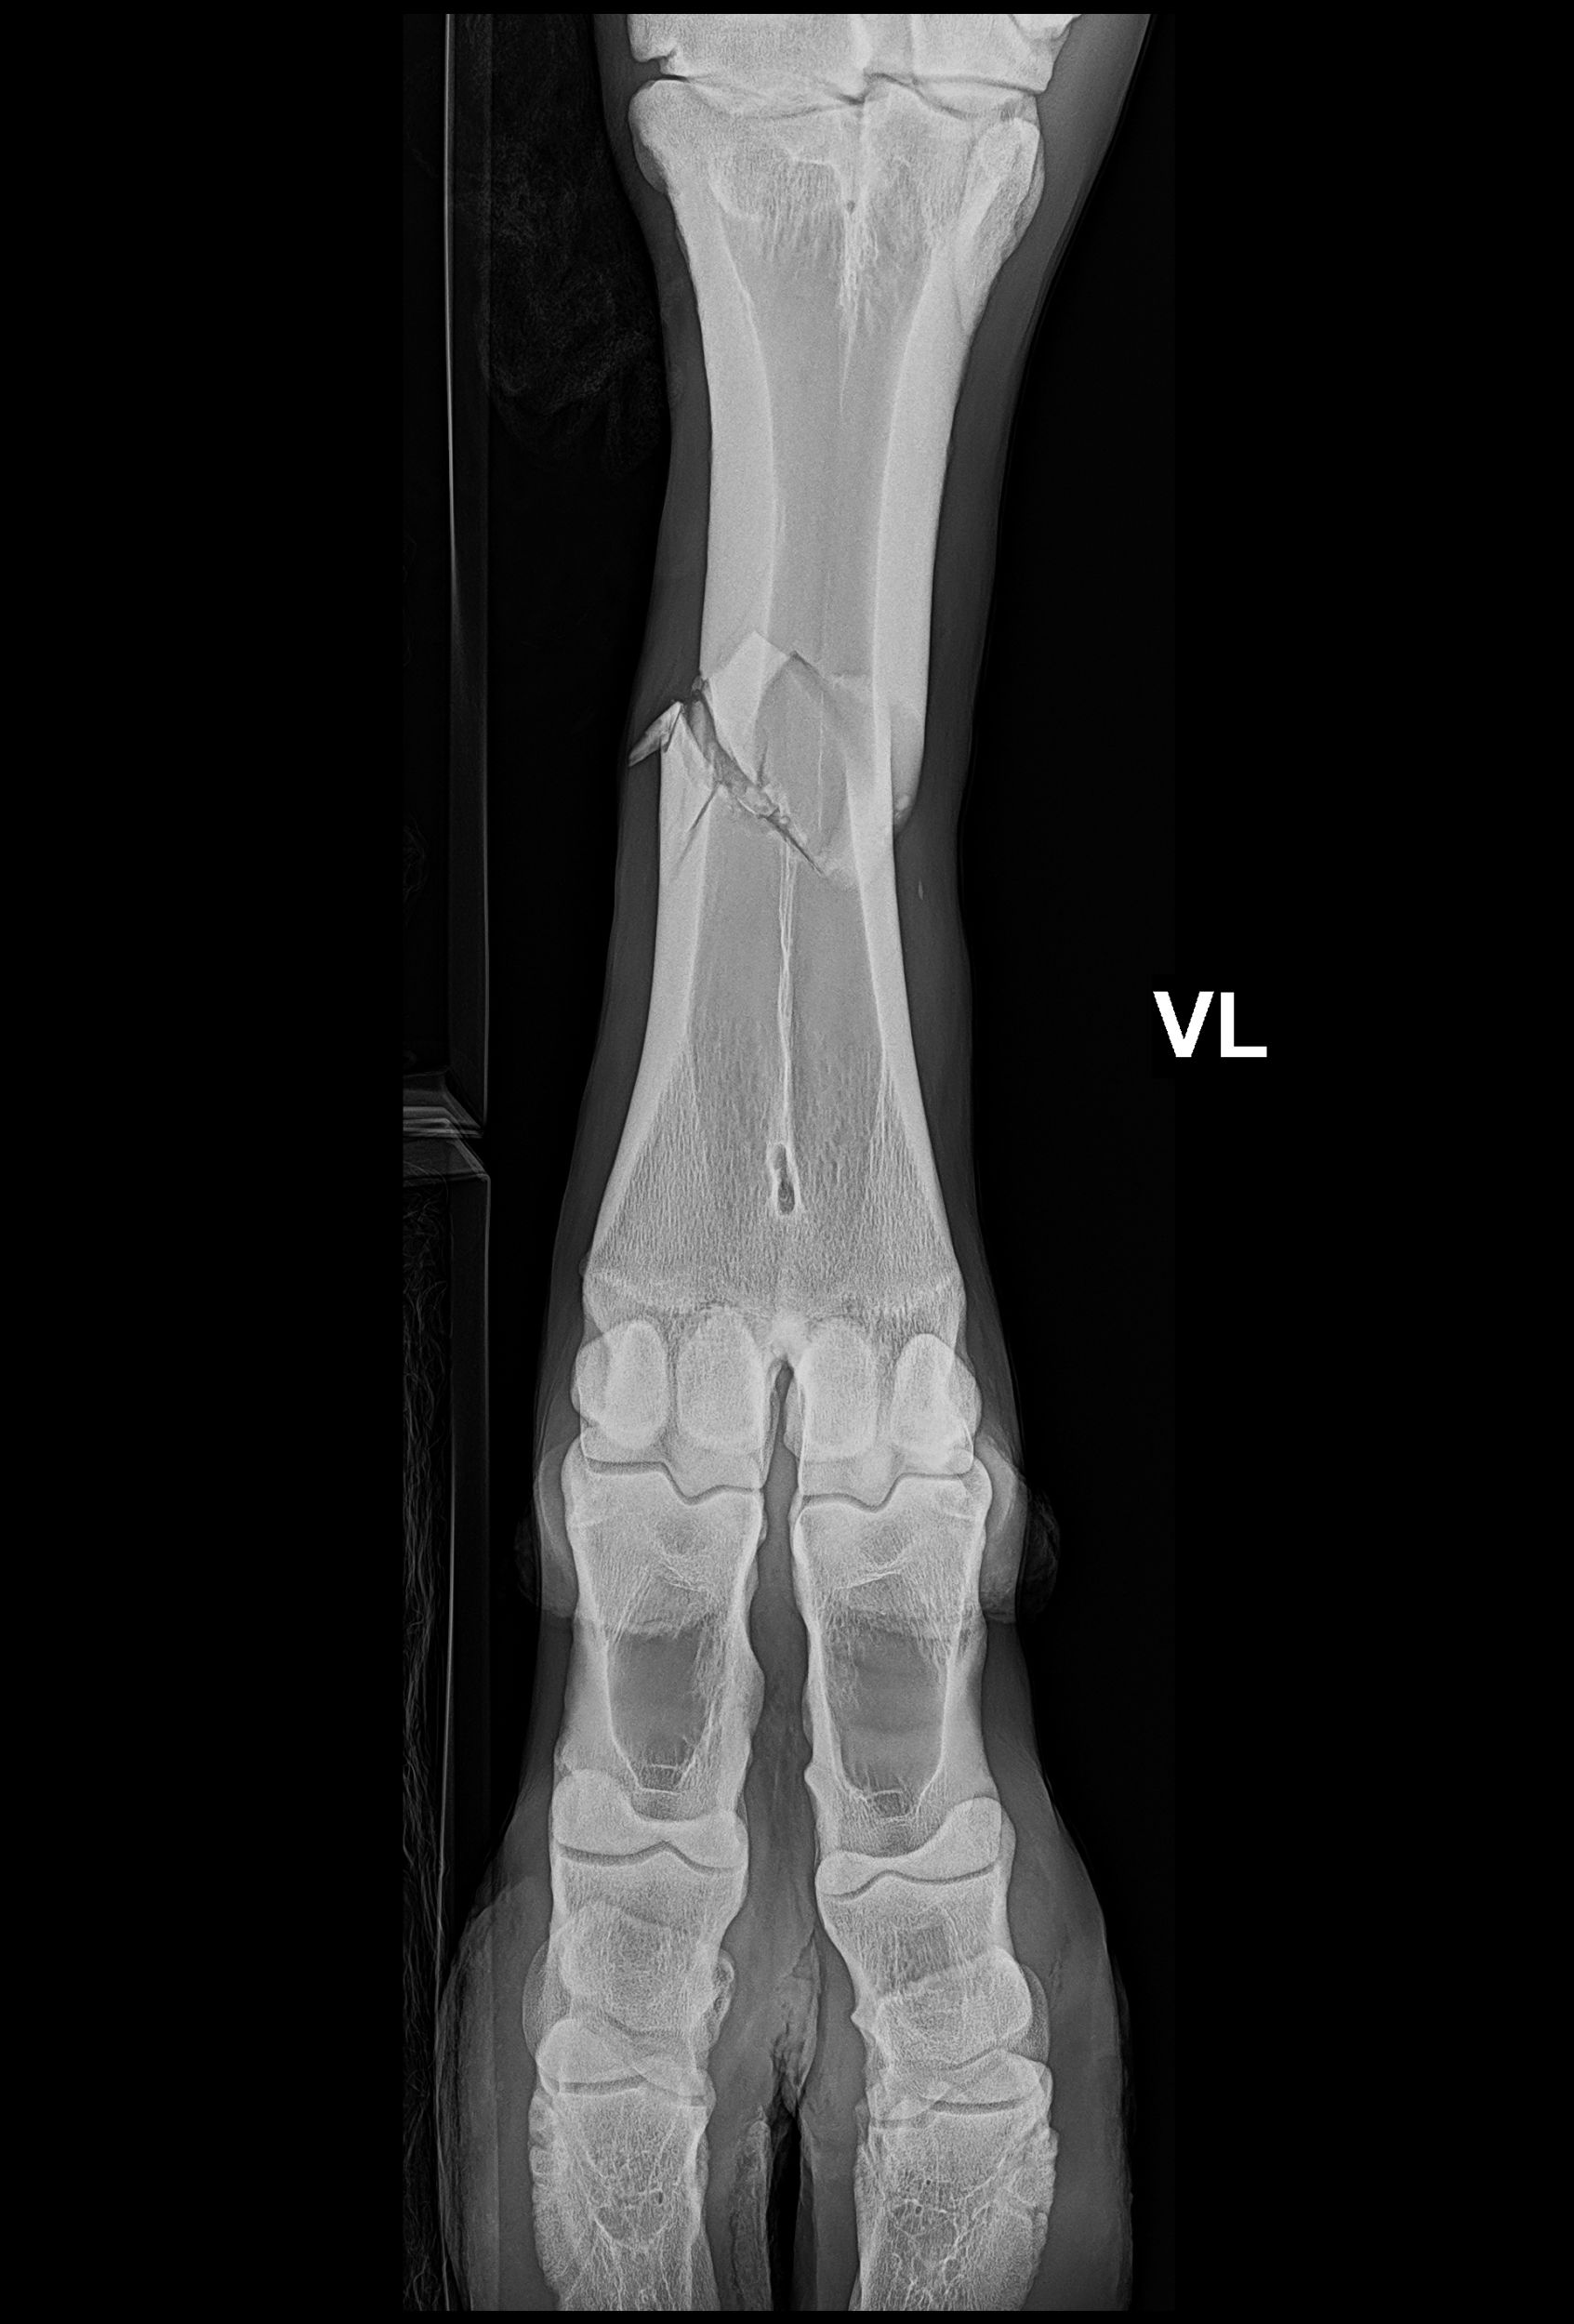

Das Bein wurde samt Gips geröntgt, man hat gesehen, dass sich der Bruch nicht verschoben hat. Der Bruch war an einer Stelle, an der eine Operation mit grossen Erfolgsaussichten theoretisch möglich war. Für Kalani gab es drei Behandlungsmöglichkeiten. Erstens: Keine Operation und das Bein nur mit Gips fixieren und stabilisieren. Zweitens: Eine Operation mit leichter Fixierung der Bruchstelle mit Schrauben und Gips. Drittens: Eine Operation mit Fixierung der Bruchstelle mit Platten und Schrauben und einem Gips.

Ich habe gesagt, wenn schon, dann die Möglichkeit mit der grössten Erfolgsaussicht und das war die Dritte. Kalani wurde am nächsten Morgen noch einmal ohne Gips geröntgt, die Ausgangslage und Erfolgschancen waren so gut, dass anschliessend in einer 5,5-stündigen Operation der Bruch fixiert wurde.